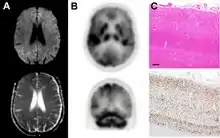

Imaging

Imaging of the brain may be performed during medical evaluation, both to rule out other causes and to obtain supportive evidence for diagnosis. Imaging findings are variable in their appearance, and also variable in sensitivity and specificity.[43] While imaging plays a lesser role in diagnosis of CJD,[44] characteristic findings on brain MRI in some cases may precede onset of clinical manifestations.[45]

Brain MRI is the most useful imaging modality for changes related to CJD. Of the MRI sequences, diffuse-weighted imaging sequences are most sensitive.[46] Characteristic findings are as follows:

Brain FDG PET-CT tends to be markedly abnormal, and is increasingly used in the investigation of dementias.

- Patients with CJD will normally have hypometabolism on FDG PET.[50]

Histopathology

Testing of tissue remains the most definitive way of confirming the diagnosis of CJD, although it must be recognized that even biopsy is not always conclusive.[51]

In one-third of people with sporadic CJD, deposits of "prion protein (scrapie)", PrPSc, can be found in the skeletal muscle and/or the spleen.[52] Diagnosis of vCJD can be supported by biopsy of the tonsils, which harbor significant amounts of PrPSc; however, biopsy of brain tissue is the definitive diagnostic test for all other forms of prion disease. Due to its invasiveness, biopsy will not be done if clinical suspicion is sufficiently high or low. A negative biopsy does not rule out CJD, since it may predominate in a specific part of the brain.[53]

The classic histologic appearance is spongiform change in the gray matter: the presence of many round vacuoles from one to 50 micrometers in the neuropil, in all six cortical layers in the cerebral cortex or with diffuse involvement of the cerebellar molecular layer.[54] These vacuoles appear glassy or eosinophilic and may coalesce. Neuronal loss and gliosis are also seen.[55] Plaques of amyloid-like material can be seen in the neocortex in some cases of CJD.[56]